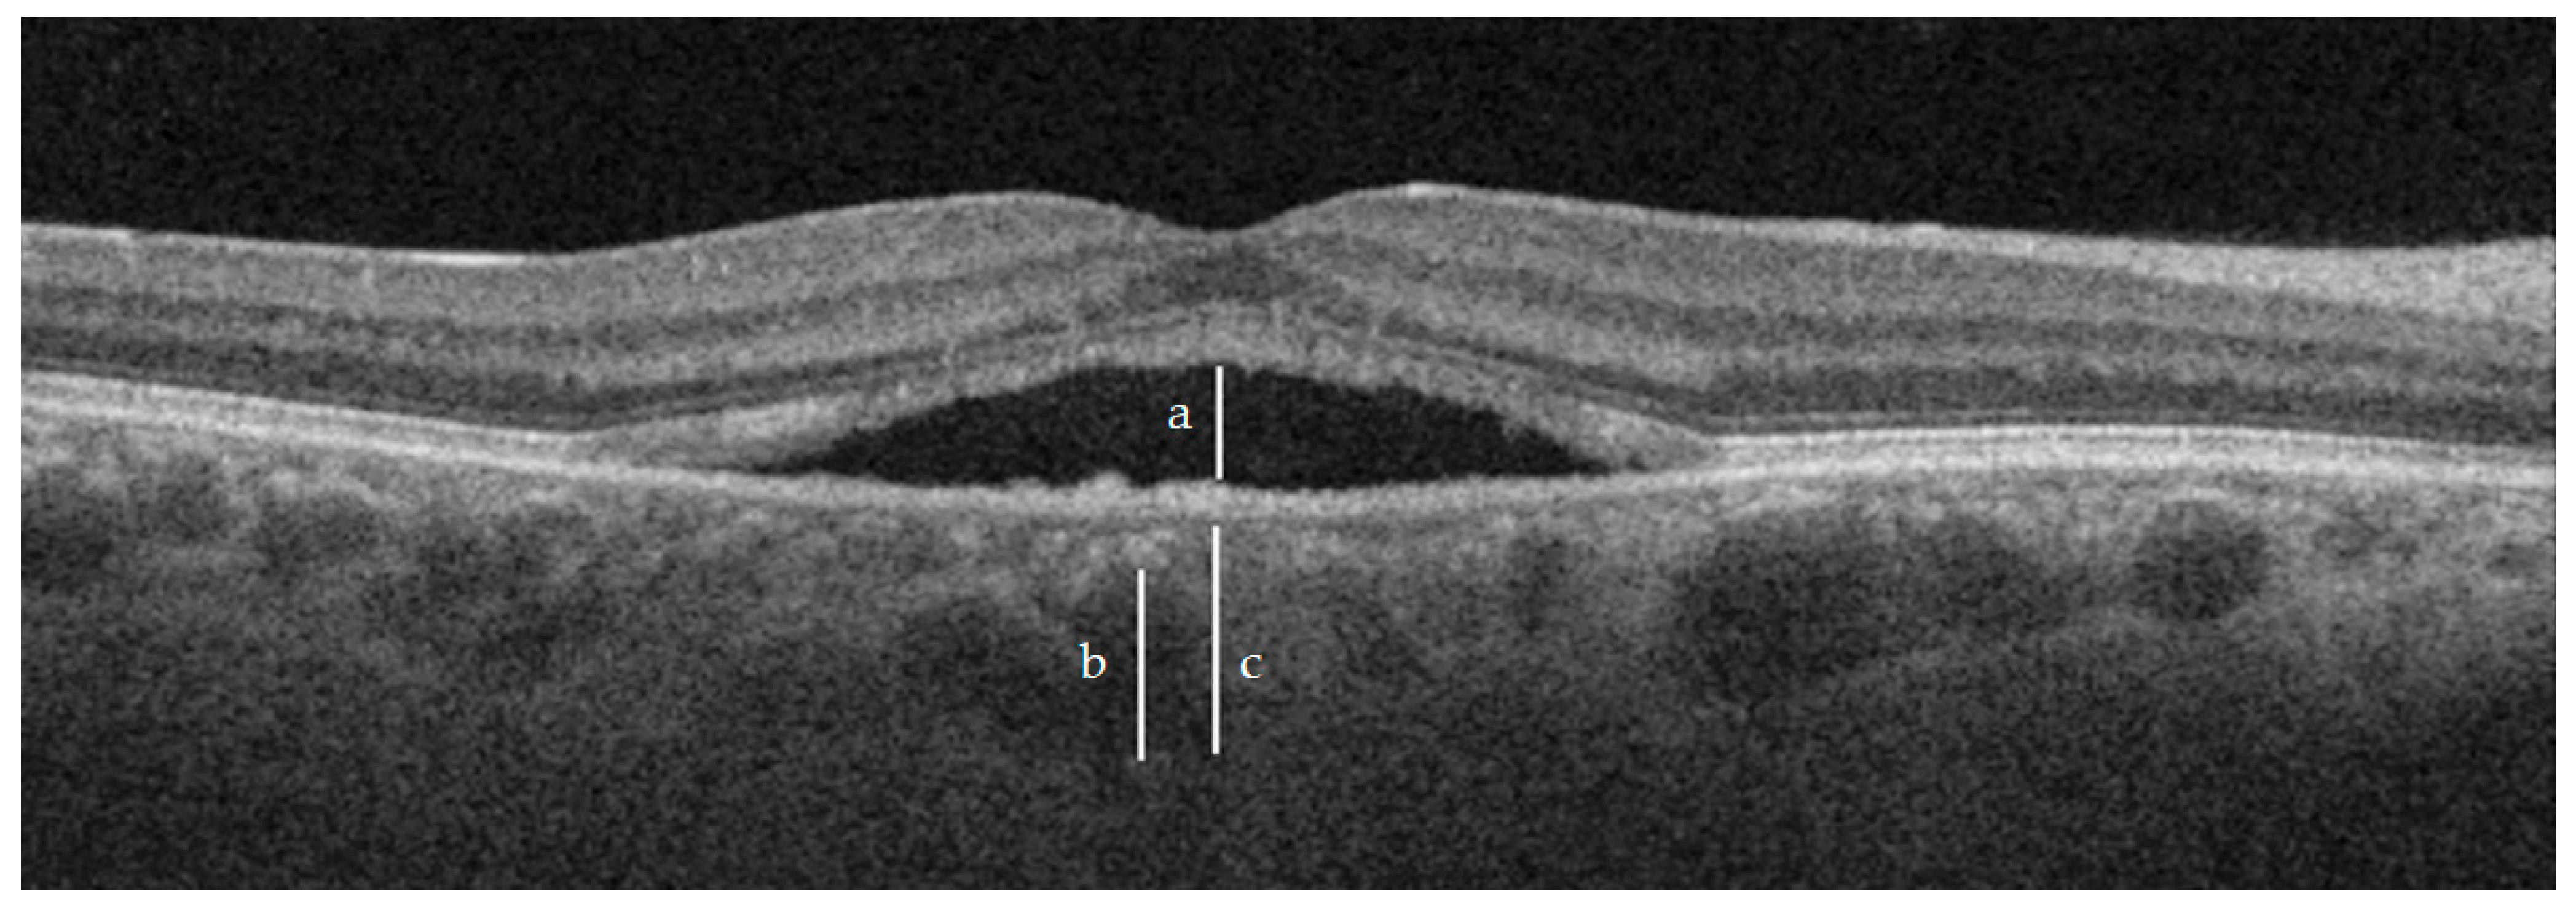

| CT | 374.9 ± 81.1 | 345.3 ± 71.5 | 0.0566 | 325.8 ± 59.2 | <0.05 | 280 ± 114.6 | <0.05 |

| Haller layer | 312.1 ± 71.3 | 287.4 ± 64.3 | 0.0953 | 274 ± 55.1 | <0.05 | 246 ± 115.9 | <0.05 |

| C-S | 62.8 ± 23.9 | 57.93 ± 20.8 | 0.3164 | 51.8 ± 18.3 | <0.05 | 34 ± 20.8 | <0.05 |